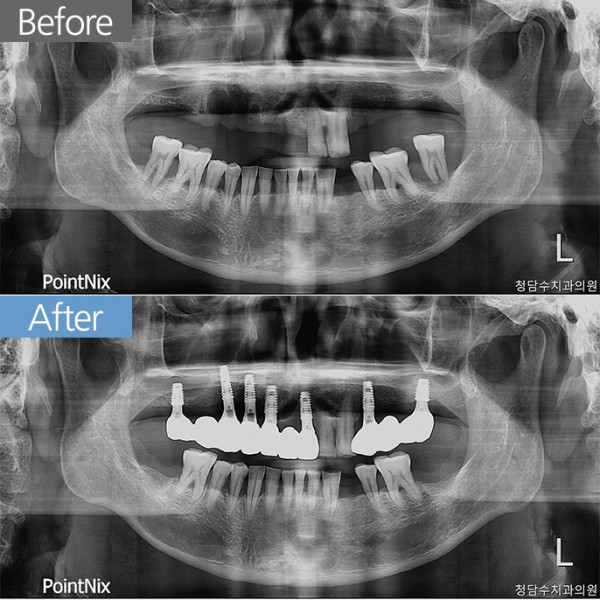

임플란트 50대남 임플란트

50대남 임플란트